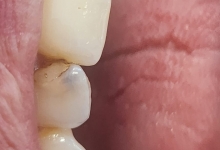

Clinica LUY ESTHETIC ART defineste parodontoza ca fiind rezultatul direct al placii dentare, care se depune pe suprafata dintilor, dar si in apropiere de marginea gingivala. Aceasta boala duce la pierderea dintilor, chiar daca ei sunt aparent sanatosi si nu prezinta carii. Edentatiile, afecteaza vorbirea, aspectul, dar si capacitatea de a mesteca.

Boala parodontala are un caracter progresiv. Pentru cazurile mai grave, recomandam tratamentul parodontal chirurgical rezectiv sau regenerativ.

– retractii gingivale cu expunerea radacinilor dentare;